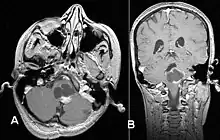

Usually – depending on the interview of the patient and after a clinical exam which includes a neurological exam and an ophthalmological exam – a CT scan and/or an MRI scan will be performed to confirm the presence of a tumor. They are usually easily distinguishable from normal brain structures using these imaging techniques. A special dye may be injected into a vein before these scans to provide contrast and make tumors easier to identify. Pilocytic astrocytomas are typically clearly visible on such scans, but it is often difficult to say based on imaging alone what type of tumor is present.